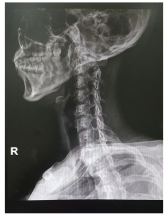

목디스크 증상 원인 치료방법 등 목 디스크 관련 정보에 대해 알아보도록 하겠습니다. 목디스크는 인간의 척추 중 경추부나 흉추부에 위치한 디스크(틀니)가 변형되어 생긴 질환으로, 경추부의 경우 목의 통증, 저림 혹은 근육 경련, 어깨와 팔의 통증, 감각상실 등이 나타나며, 흉추부의 경우 흉부의 통증, 등의 통증 등이 나타납니다. 보통은 원인불명성으로 인한 자연적인 회복을 기다리는 것이 가장 좋으며, 통증이 심한 경우 보조적으로 항통제나 근육 이완제 등을 사용합니다. 만약 압력이 심한 경우 수술이 필요할 수 있습니다.예방법으로는 바른 자세 유지와 체중 조절, 충분한 운동, 목과 등의 근육 강화 등이 있습니다.

목 디스크는 경추부나 흉추부의 디스크(틀니) 변형으로 인해 발생하는 질환으로, 다음과 같은 증상이 나타날 수 있습니다.

목 디스크 원인

목 디스크는 디스크(틀니)가 변형되어 생기는 질환으로, 다음과 같은 원인이 있을 수 있습니다.